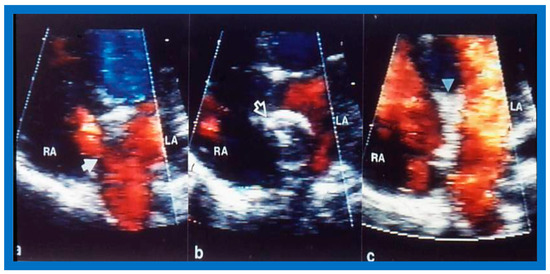

9. Follow-Up after Device Occlusion